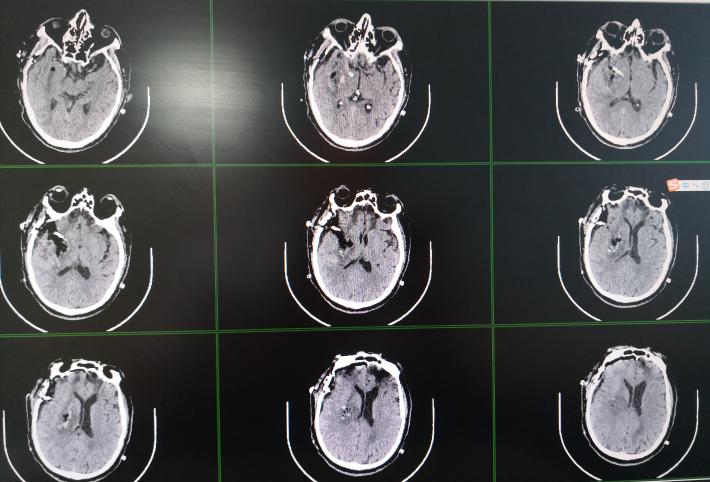

70岁男性,以“突发意识不清1天”从外院转入。1天前情绪激动时突然晕倒,失语,意识不清,左侧上、下肢体不能活动,在外院行头颅 CT:“右侧基底节脑出血”。既往无“高血压”病史,10余年前有“颅脑外伤”病史,平时左下肢跛行。腰椎骨折手术病史。查体:浅昏迷,GCS评分E3V1M4。刺激右侧上下肢能屈曲活动,左侧上下肢不能活动。双侧巴氏征阴性。

右侧基底节脑出血。

术后复查头部CT:脑内血肿几乎全部清除。